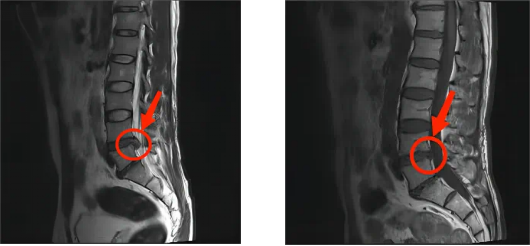

出院后一年,王先生来院复查,通过医学仪器看到椎间盘明显回缩。

术前MR,L4/5椎间盘明显突出 术后1年复查MR,L4/5椎间盘回缩明显